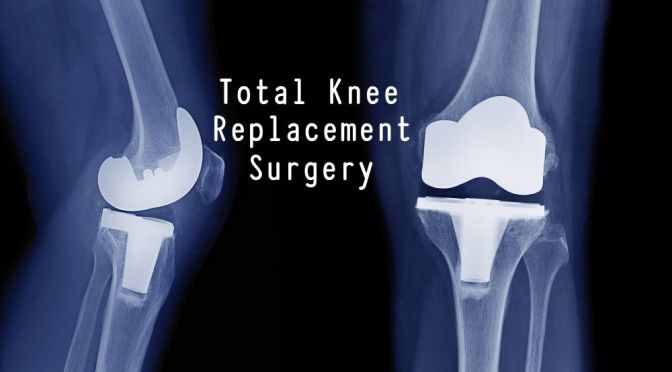

Total knee replacement(arthroplasty) is one of the most successful orthopedic operations. Satisfaction rate varies between 75 and 90%. Even so, almost 10% of operated individuals will have anterior knee pain, the most common complication, 1 year after TKR.

With knee replacement surgery, a great deal depends on the technical expertise and precision of the operating surgeon. A rotational error more than a degree or two can be critical, so important is proper tracking of the kneecap in the trochlea, or groove in the leg bone(femur). An imbalance in the pull of muscles, or a knock knee, (Valgus) angulation of the knee, hip rotation, spinal problems, all can be important in generating pain as you get older.